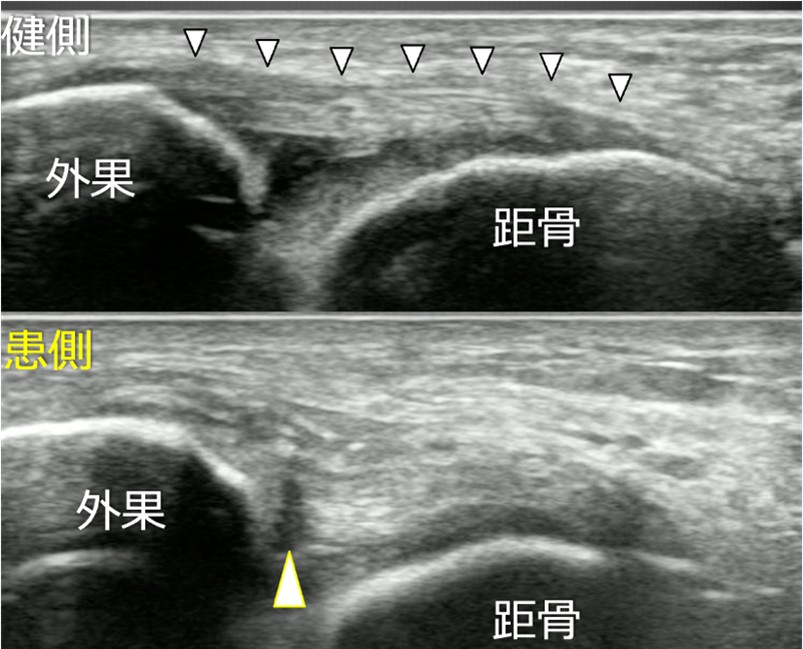

スポーツ傷害の診療において、適切な画像診断を行うことは大切です。現在の超音波検査は、レントゲンでは直接見ることが出来ない靱帯や腱の損傷部位を鮮明に描出することができ、従来のMRIやCTとは異なり「動き」の中で診断することが可能です(図1)。

足関節外側靭帯損傷

足関節外側靭帯損傷はいわゆる足関節捻挫で受傷することが多い、スポーツ傷害の中で最も頻度の高いものの一つです。そのほとんどが保存治療で治癒すると考えられがちですが、最新の研究によると30%前後は慢性化し、足関節の不安定性や疼痛が残存し、スポーツ活動や日常生活に支障ときたしていることが知られています。

リハビリテーションや投薬治療で改善がみられない場合は、手術治療が適応となることがあります。

手術は関節鏡を併用して、スーチャーアンカーを用いて外側靭帯を修復します(図13)。